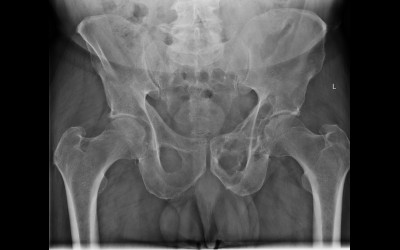

76 jähriger Patient mit diffusen Skelettschmerzen Keine Grunderkankung bekannt, kein Trauma.

Becken ap